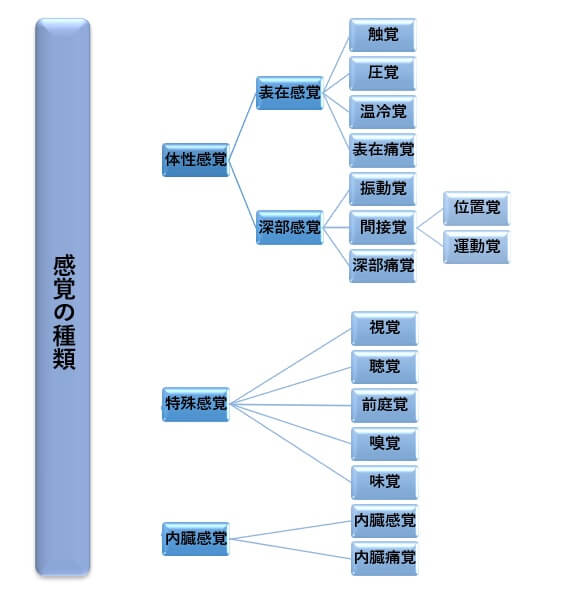

感覚の種類にはどんなものがある?

体性感覚は、大きく分けて表在感覚と深部感覚があり、身体のさまざまな部位から感じる感覚のことを指します。具体的には以下のような種類があります。

特殊感覚は、私たちが外界と繋がる独特な感覚を指します。

一方、内蔵感覚は、体の内部からの情報を感知する感覚です。おなかがすいたり、のどが乾いたりするときの感覚や、内臓の痛みを知覚する感覚がこれに該当します。すべて、私たちの生活に欠かせない大切な感覚です。

表在感覚

触覚:物に触れたときの感覚。

圧覚:何かに押されるときの感じる感覚。

温冷覚:身体が温かいものや冷たいものを感じ取る感覚。

表在痛覚:皮膚の表面などが傷ついたときの痛みの感覚。

深部感覚

振動覚:身体が振動をキャッチする感覚。

関節覚:手や足の位置や動かす方向を知覚する感覚。(具体的には、位置覚:身体の部分がどこにあるのかを感じる能力、運動覚:身体の動く方向を感じる能力)。

深部痛覚:筋肉や骨の内部などの深い部分が傷ついたときの痛みの感覚。

特殊感覚

視覚:光や風景を見る感覚。

聴覚:音を感じる感覚。

前庭覚:動きやバランス、頭の傾きや回転を知覚する感覚。

嗅覚:鼻で香りや臭いを嗅ぐ感覚。

味覚:舌で食べ物や飲み物の味を味わう感覚。

内臓感覚

内臓感覚:おなかがすいたり、のどが乾いたりすると感じる感覚。

内臓痛覚:体の内部、特に内臓が痛むときの感覚。